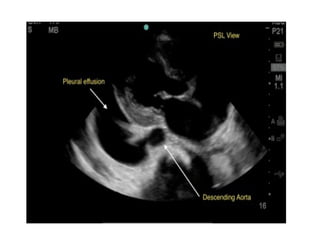

Scans are obtained at 4 interfaces:

•Pericardial sac

•Hepatorenal interface

•Splenorenal interface

•Pelvis interface

Pericardial interface